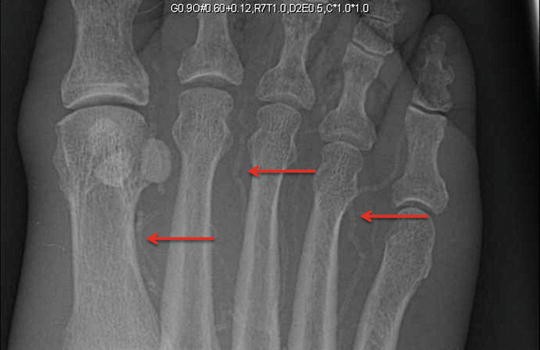

Original Resolution: 558x859 Jbjs Search This is a proposed classification system for radiologists in the netherlands and still work in progress. 600x378 - The radiology team at cambridge health alliance provides expert imaging services at cha hospitals and community locations, using the latest tools and technology.